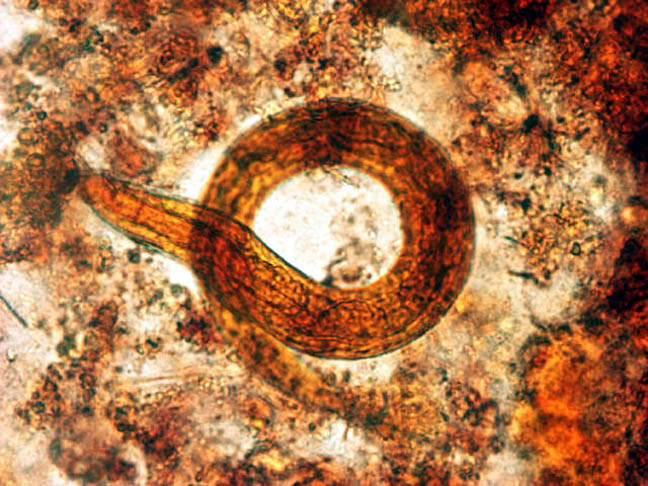

- 40x

Stongyloides

Notice how the larvae are normally curved